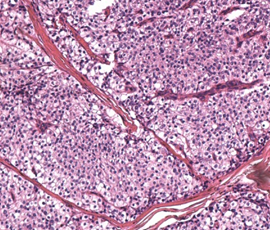

Histopathological examination of parathyroid adenocarcinoma (Courtesy Dr. V. Penopoulos)